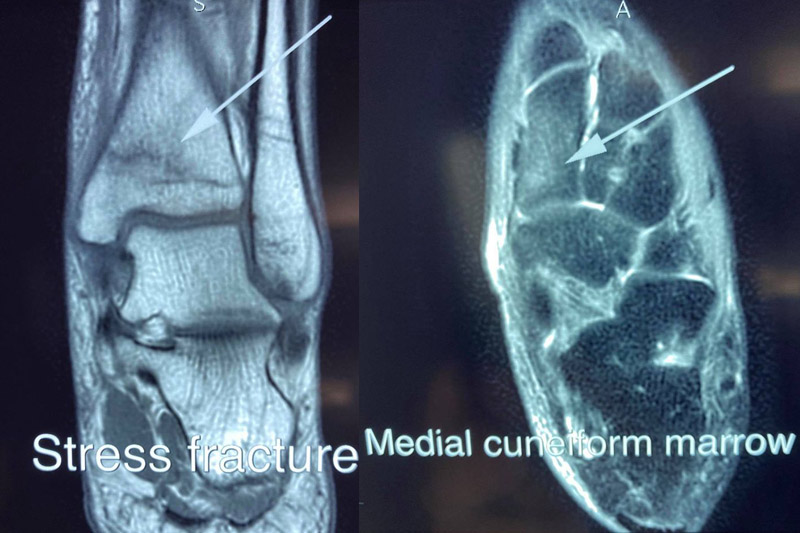

骨科專科醫生黃仕雄於臉書專頁「樹熊醫生」分享,指最近遇到一名年約40歲病人求診,稱突然出現沒有原因的腳痛。患者沒有受傷病史,也沒有瘀青,X光及血液檢查結果正常,唯一病徵是「行路時間越長越痛」,經MRI檢查後,證實脛骨骨折。

於是,黃醫生再三追問,患者原來每天都會與家人玩1至2小時健身環運動遊戲,在家中「赤腳」原地跑跳數小時,誘發「壓力性骨折」(stress fracture)。